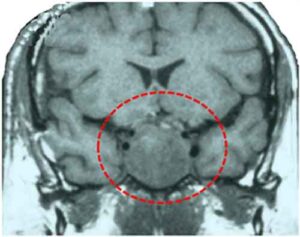

La ghiandola pituitaria e’ un organo a forma di pera posto alla base del cervello. Dal punto di vista della rigenerazione con cellule staminali, si tratta di una vera sfida per gli scienziati, perche’ e’ formata da due parti distinte e secerne almeno otto tipi diversi di ormoni che regolano crescita, fertilita’, produzione di latte, pressione sanguigna, temperatura e altre funzioni.